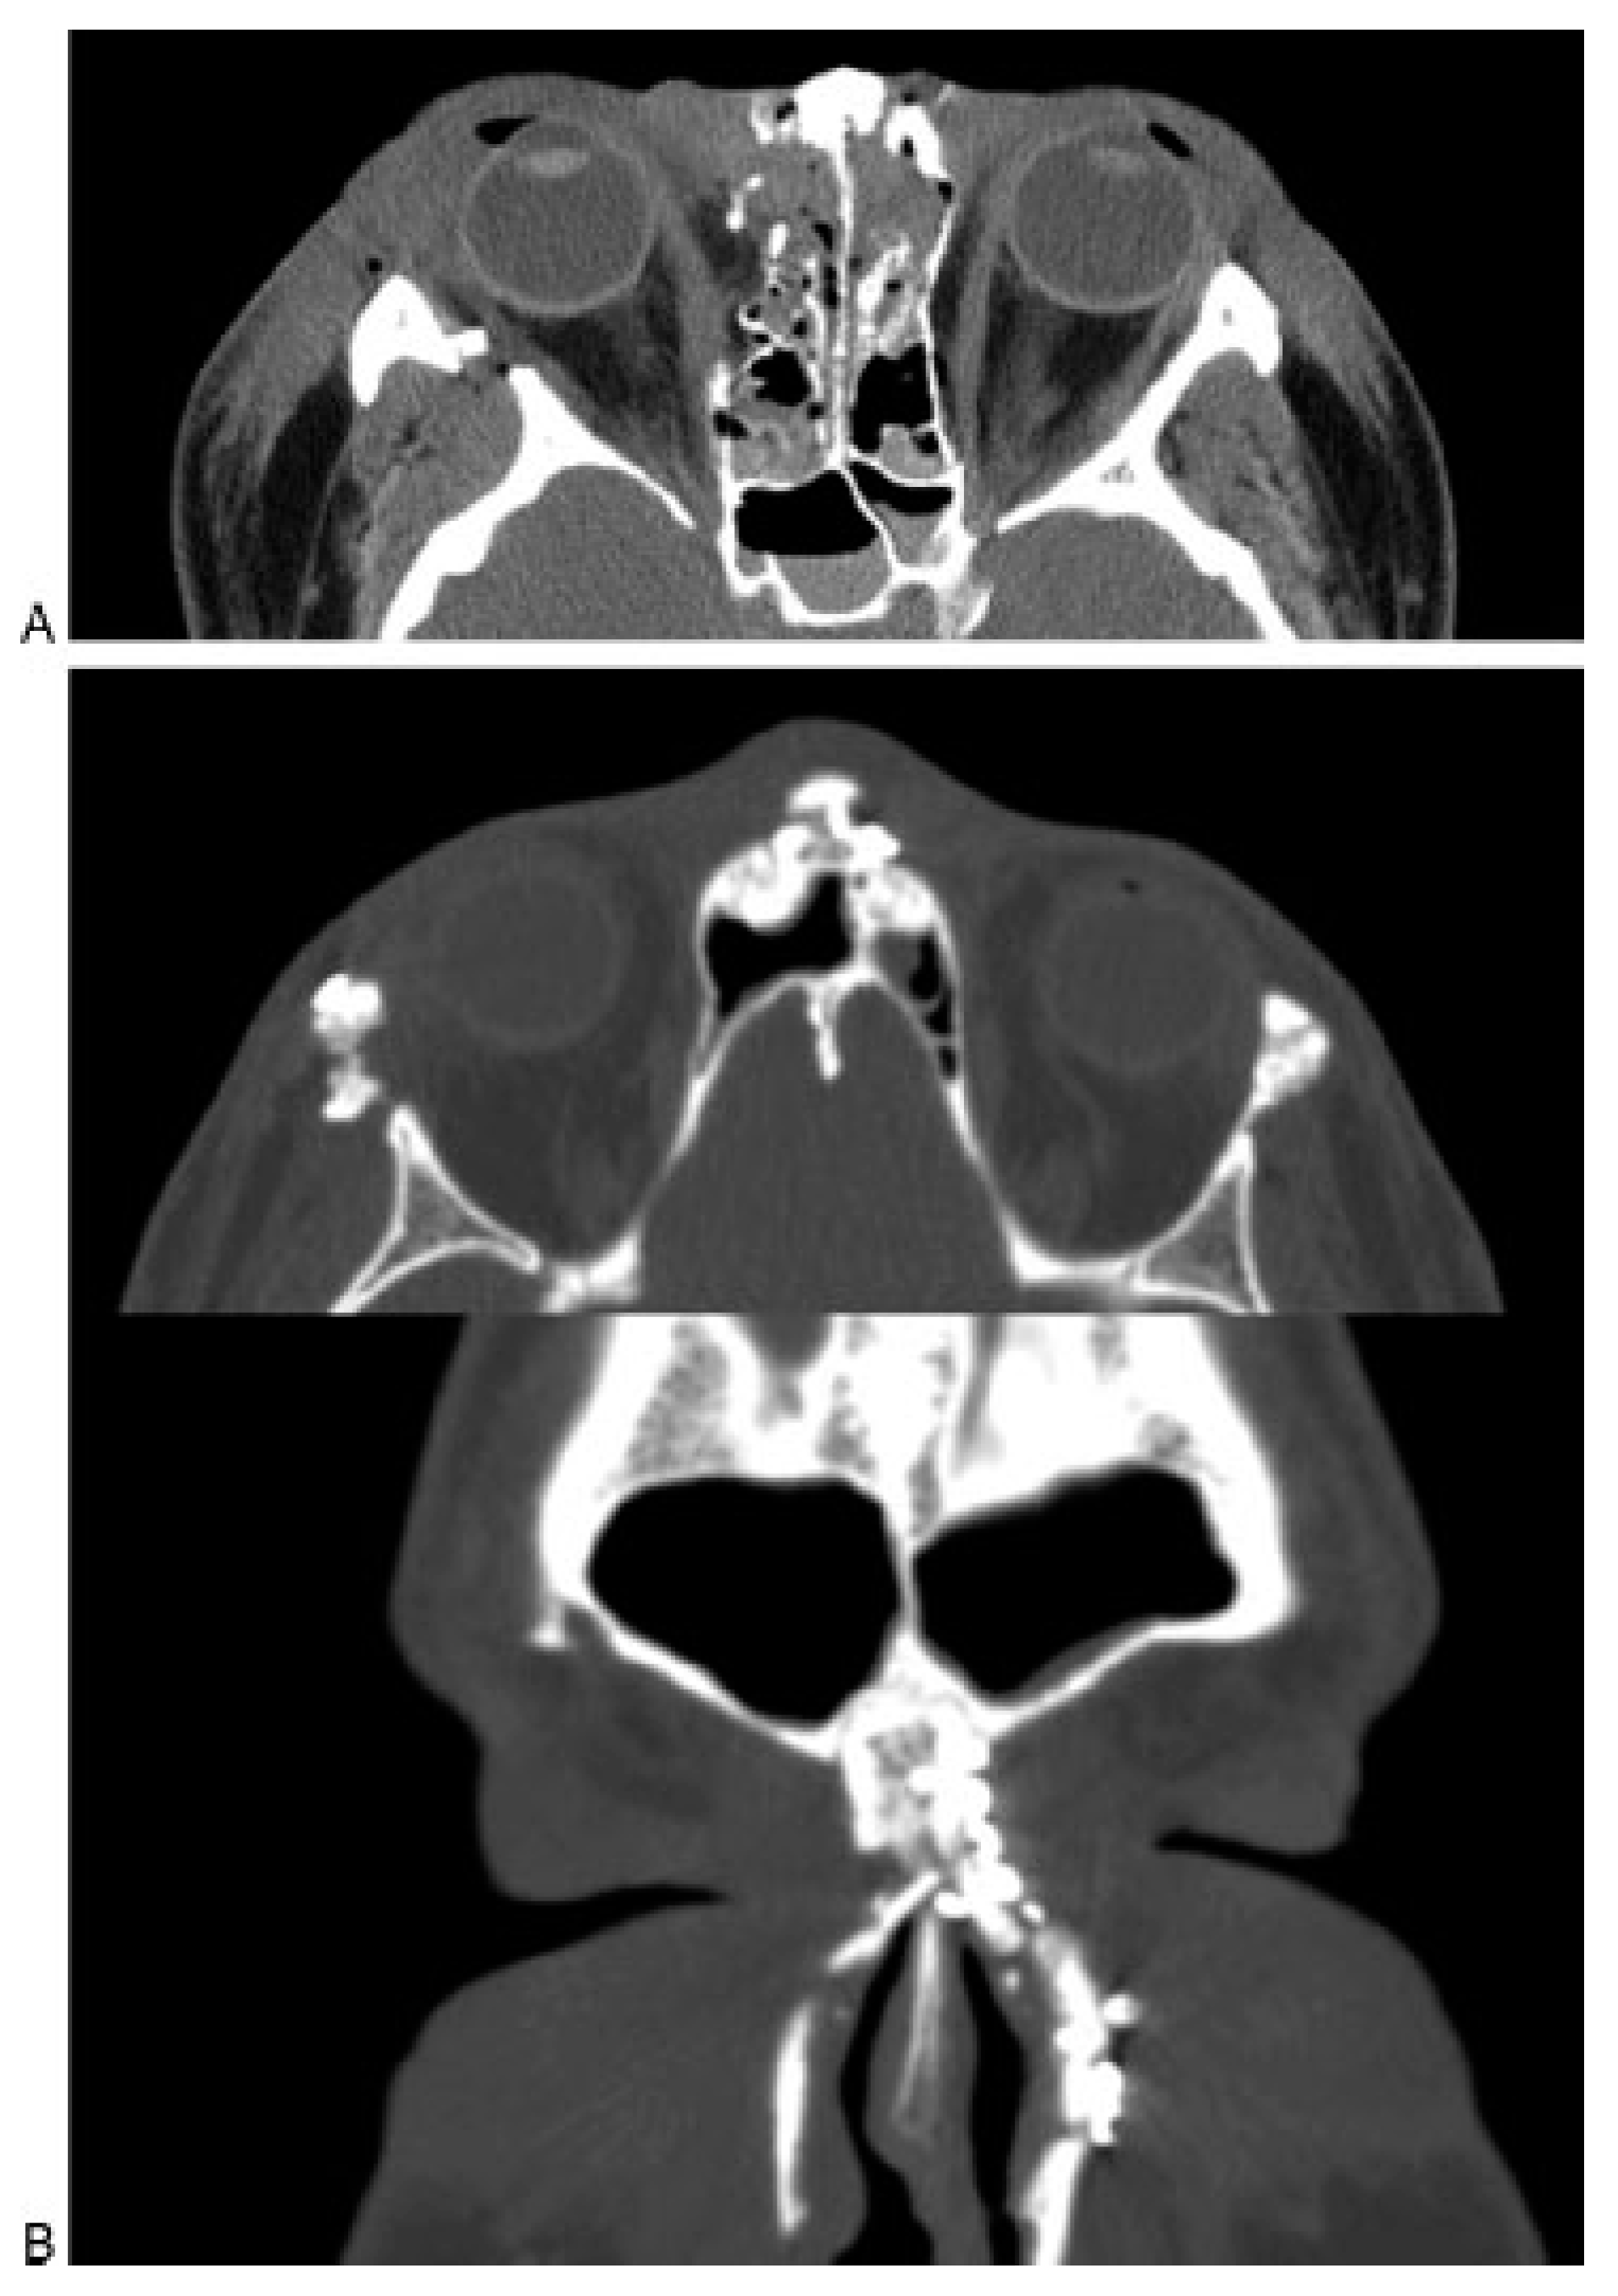

Frontal recess fractures result in disruption of the only frontal sinus outflow tract. Regardless of anterior or posterior table injuries, frontal recess fractures that result in sinus outflow obstruction will generally require frontal sinus obliteration. Due to the compact nasofrontal anatomy, accurate diagnosis of a frontal recess injury on CT can be difficult to accurately assess. One option (used infrequently by the author) is to perform a frontal sinus trephination and visualize the recess endoscopi- cally. If the frontal recess patency remains in question (and there are no other significant sinus injuries), pa- tients may be followed clinically and with sequential CT scans at ~3 and 12 months to ensure that the sinus is patent and no frontal recess stenosis has occurred. Smith et al. described some success with expectant observation of frontal recess fractures. After open reduction and internal fixation of the frontal sinus anterior table and naso-orbito-ethmoid injuries, the patients were followed with serial CT scans [9]. They reported spontaneous ven- tilation of the sinus in five of seven patients. Two patients had persistent obstruction requiring an endo- scopic frontal sinusotomy. At the time of publication, these two patients had adequate sinus ventilation (21 and 25 months), and no patients had recurrent infection or mucocele formation (mean follow-up 17 months). The current author has a series of 10 patients being treated in a similar fashion and has noted no complications or need for endoscopic sinusotomy to this point (unpublished data) (Figure 8A,B). Although early reports on this tech- nique are promising, endoscopic frontal sinusotomy following frontal recess trauma can be technically chal- lenging and should be reserved for surgeons with ex- tensive experience in both endoscopic sinus surgery as well as open approaches to the frontal sinus.

Figure 8.

(A) Axial computed tomography (CT) scan of an acute frontal sinus injury, showing partial disruption of the frontal recess. (B) Postoperative axial and coronal CT scan of the same patient demonstrating resolution of mucosal edema and patency of the frontal recess. The frontal sinus injury was observed and no frontal sinusotomy was per- formed.